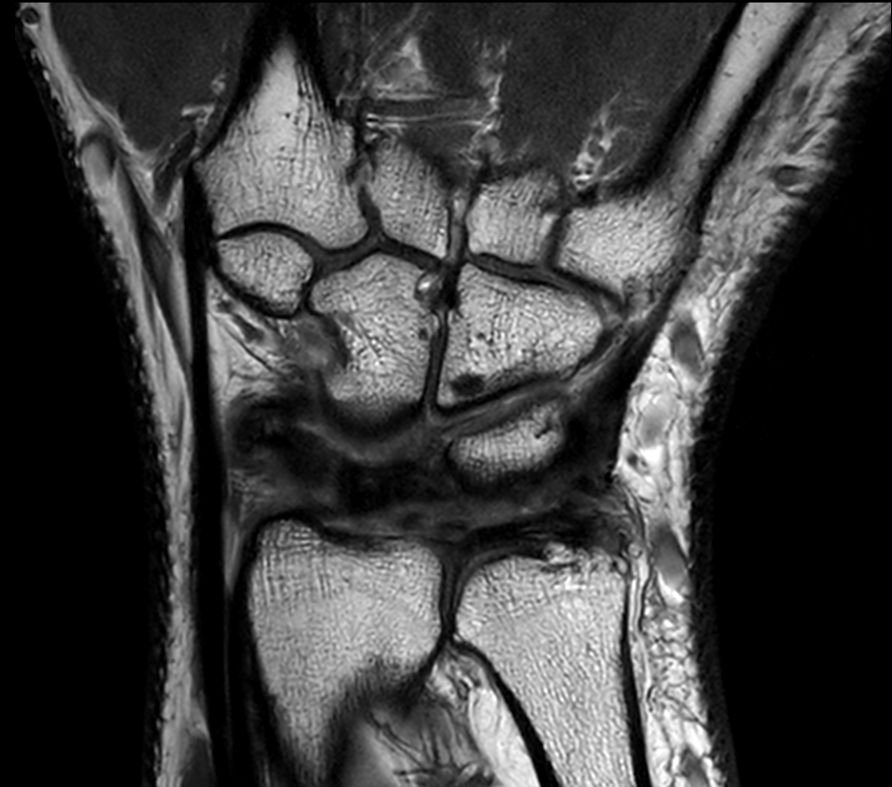

Off-center imaging of the Wrist with the dS HandWrist 16ch coil. Compressed SENSE is used to speed up the entire exam with virtually equal image quality.2.